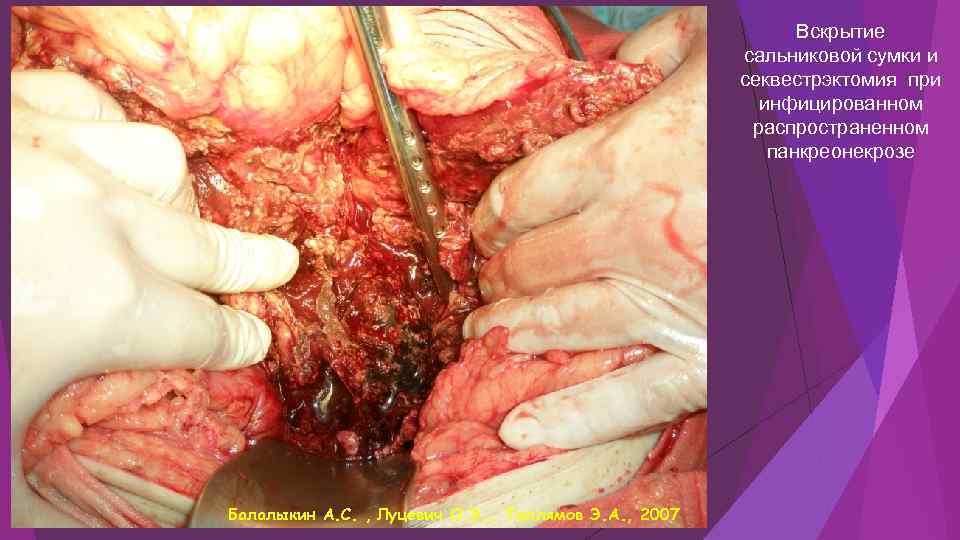

Вскрытие сальниковой сумки и секвестрэктомия при инфицированном распространенном панкреонекрозе Балалыкин А. С. , Луцевич О. Э. , Галлямов Э. А. , 2007

Вскрытие сальниковой сумки и секвестрэктомия при инфицированном распространенном панкреонекрозе Балалыкин А. С. , Луцевич О. Э. , Галлямов Э. А. , 2007

Инфицированный панкреонекроз инфицированный панкреонекроз представлен серо-черной неоднородной массой замазкообразной консистенции, не имеющий капсулы - стенки или сформировавшейся капсулы с мутным, типа «мясных помоев» или гнойным эксудатом с микроабсцессами в паренхиме и забрюшинной клетчатке. Балалыкин А. С. , Луцевич О. Э. , Галлямов Э. А. , 2007

Инфицированный панкреонекроз инфицированный панкреонекроз представлен серо-черной неоднородной массой замазкообразной консистенции, не имеющий капсулы - стенки или сформировавшейся капсулы с мутным, типа «мясных помоев» или гнойным эксудатом с микроабсцессами в паренхиме и забрюшинной клетчатке. Балалыкин А. С. , Луцевич О. Э. , Галлямов Э. А. , 2007